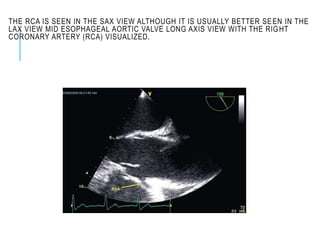

CORONARY OSTIA

The coronary ostia are well seen in the mid esophageal

AV short (left [LCA] and right [RCA]) and AV long (RCA)

axis views.

In the SAX view the left main stem (LMS) and proximal

portion of the anterior descending (LAD) and circumflex

(LCx) branches can be seen

THE RCA IS SEEN IN THE SAX VIEW ALTHOUGH IT IS USUALLY BETTER SEEN IN THE

LAX VIEW MID ESOPHAGEAL AORTIC VALVE LONG AXIS VIEW WITH THE RIGHT

CORONARY ARTERY (RCA) VISUALIZED.

THE RCA ISSEEN IN THE SAX VIEW ALTHOUGH IT IS USUALLY BETTER SEEN IN THE LAX VIEW MID ESOPHAGEAL AORTIC VALVE LONG AXIS VIEW WITH THE RIGHT CORONARY ARTERY (RCA) VISUALIZED.